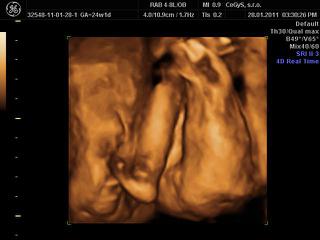

ahojte, my sme dnes boli na 3D, takže sme plní zážitkov 😀

no, princeznička je to na 100 percent 😎 😎 😎 veľmi sa tešíme. Na začiatku sa nám ukazovala pekne, potom už sme ju asi otravovali tak sa zabárala noštekom do placenty a nechcela sa ukázať.. ale máme asi 10 videosekvencií a 10 fotiek takže super!!!!

@alena24 no spolupracovala prvych 10 minut potom sme ju len tahali zo strsny na stranu, opica jedna, ale stihli sme to na zaciatku ponahravat, sme sa poucili z morf.uzv, tam sa nam tiez schovavala!!! Ano aj nas meral, zodpovedame presne tt, cize 24,4 tt a vazime 670 g. Aj nam ukazoval nejaky graf k tomu a ideme pekne stredom, co je priemer tak ako ma byt.